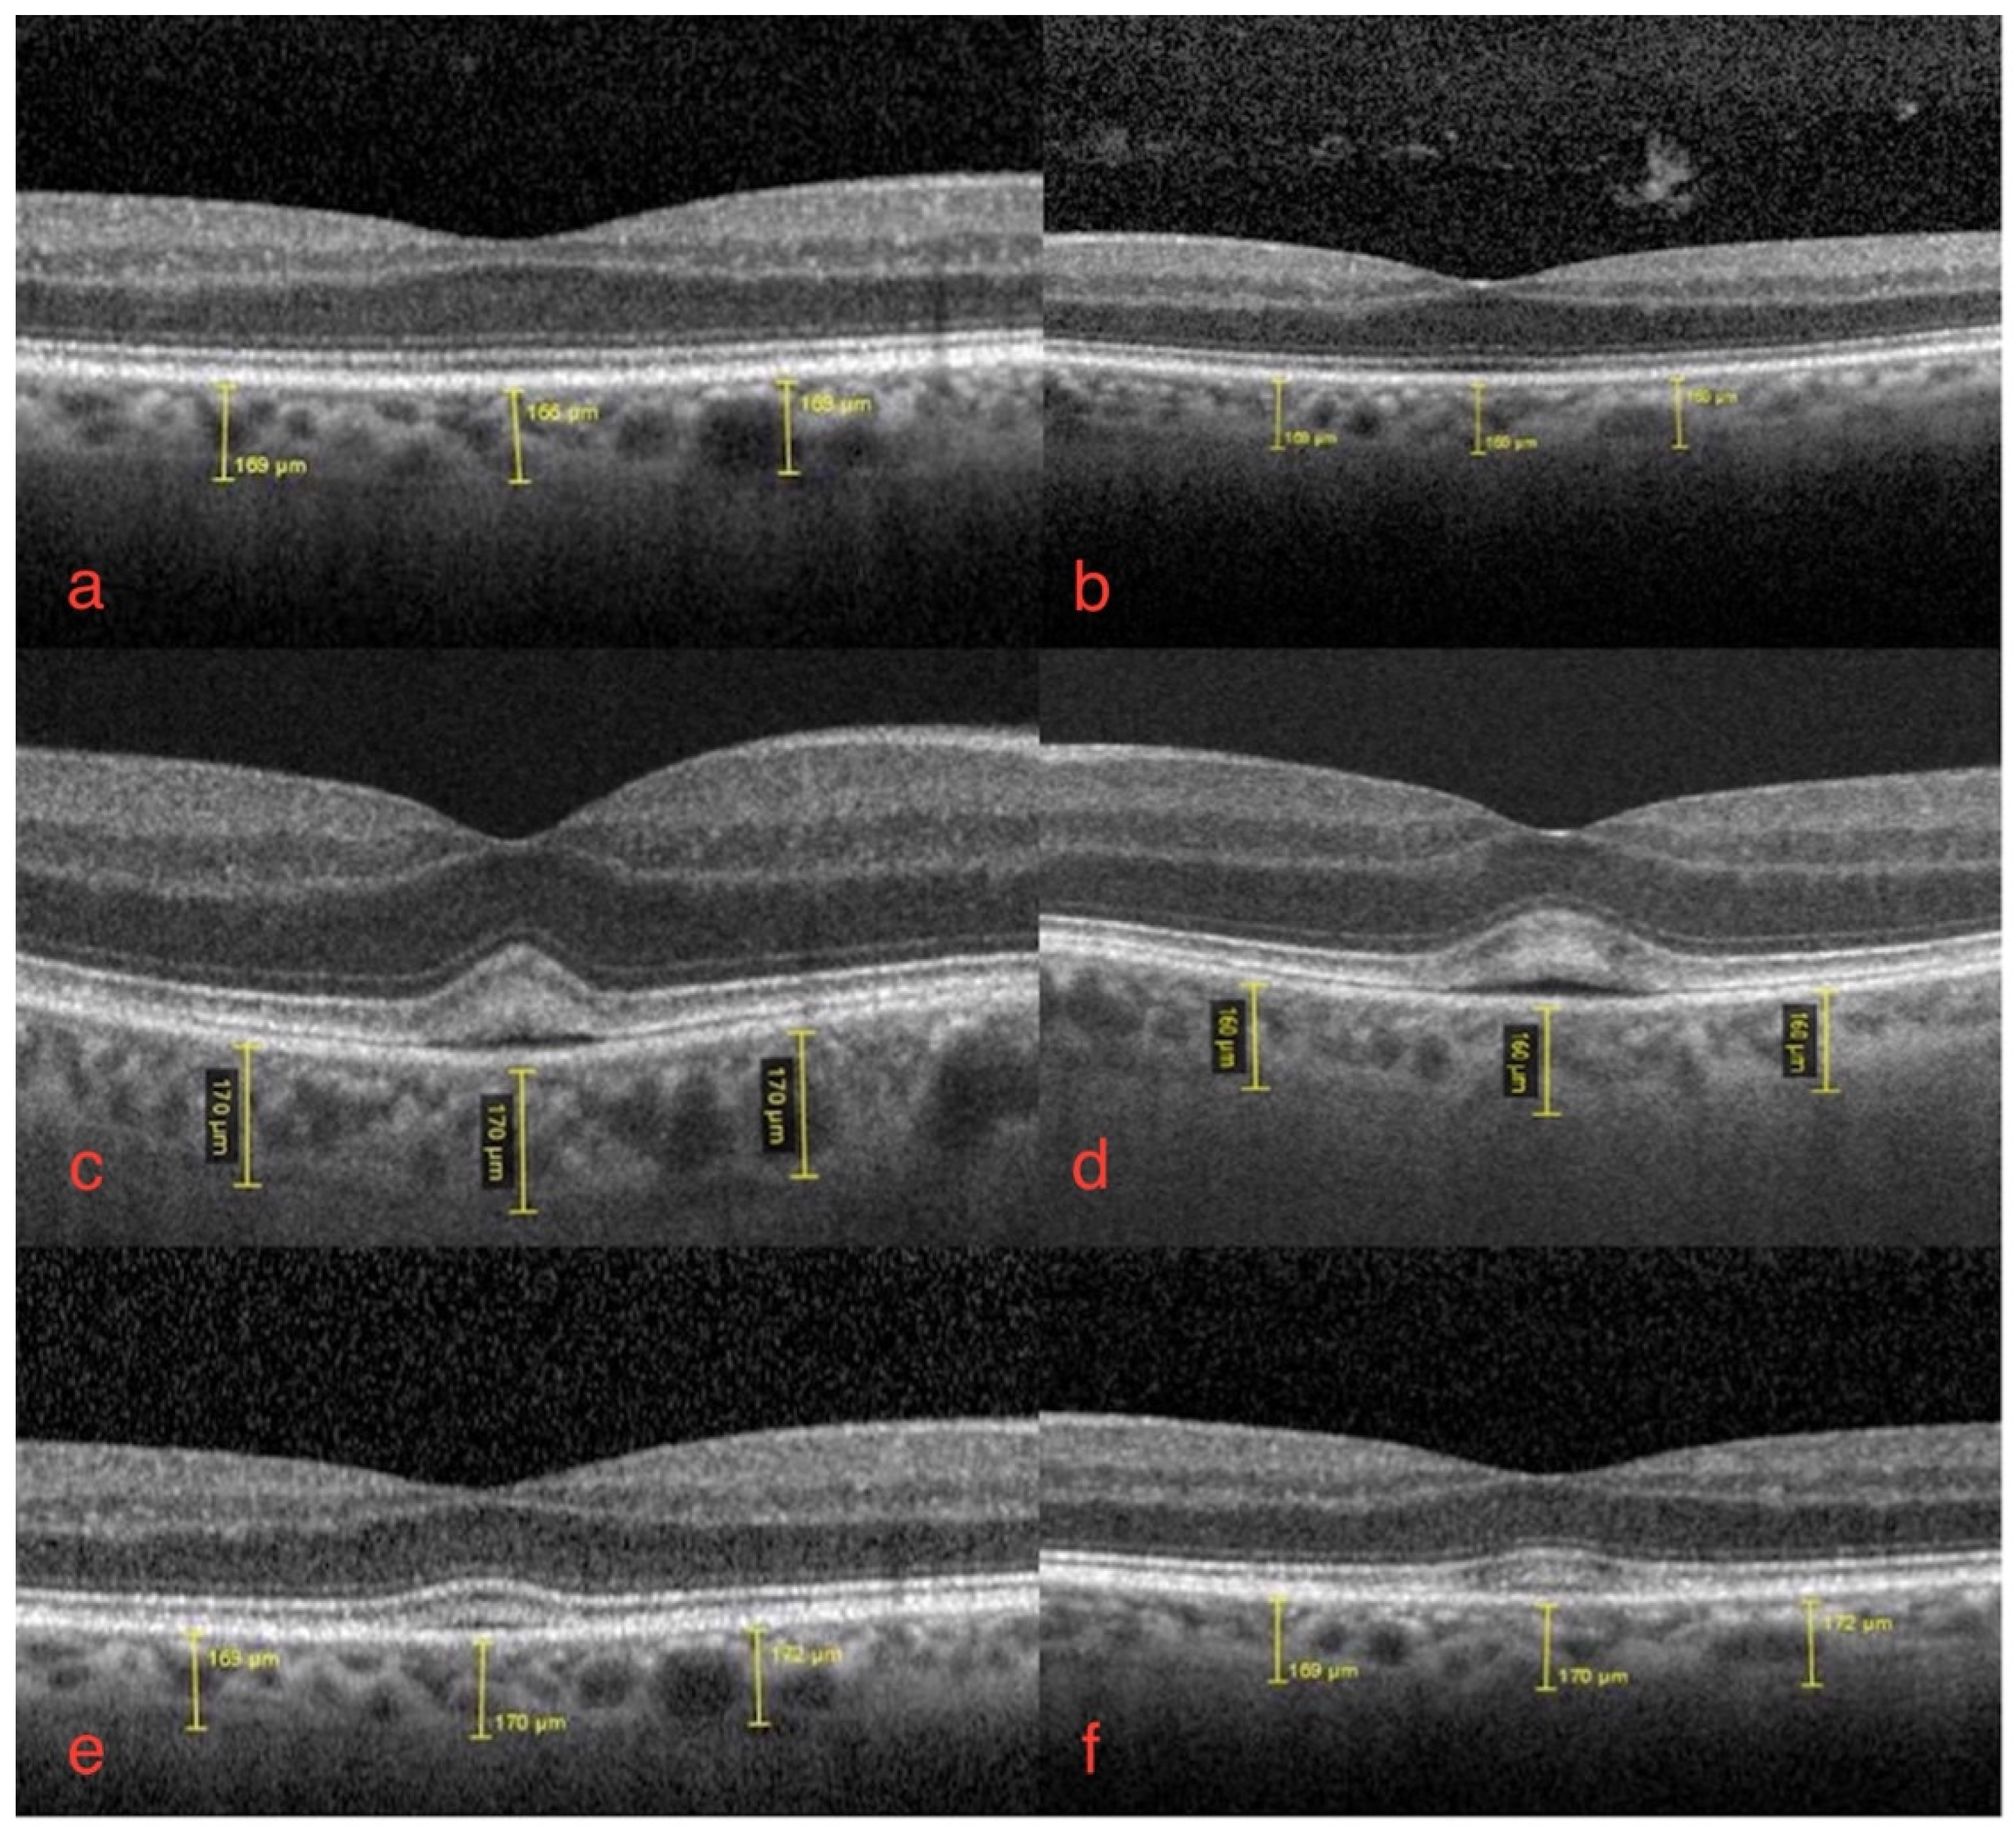

The ophthalmological findings showed bilateral decreased best-corrected visual acuity to 20/25. An absence of the normal foveal reflex was noticed upon fundoscopy. A macular OCT showed bilateral serous neuro-retinal detachment (Figure 1c,d). Fluorescein angiography (FA) was performed and revealed no leakage in either eye and no sign of retinal pigmented epithelium (RPE) alteration (Figure 2a,b). Fundus autofluorescence (FAF) imagining was normal (Figure 3a,b).

Figure 2.

Fluorescein angiography of right (a) and left eye (b).

Bilateral FGFRARshows no signs of staining or leakage in fluorescein angiography mid-phase.